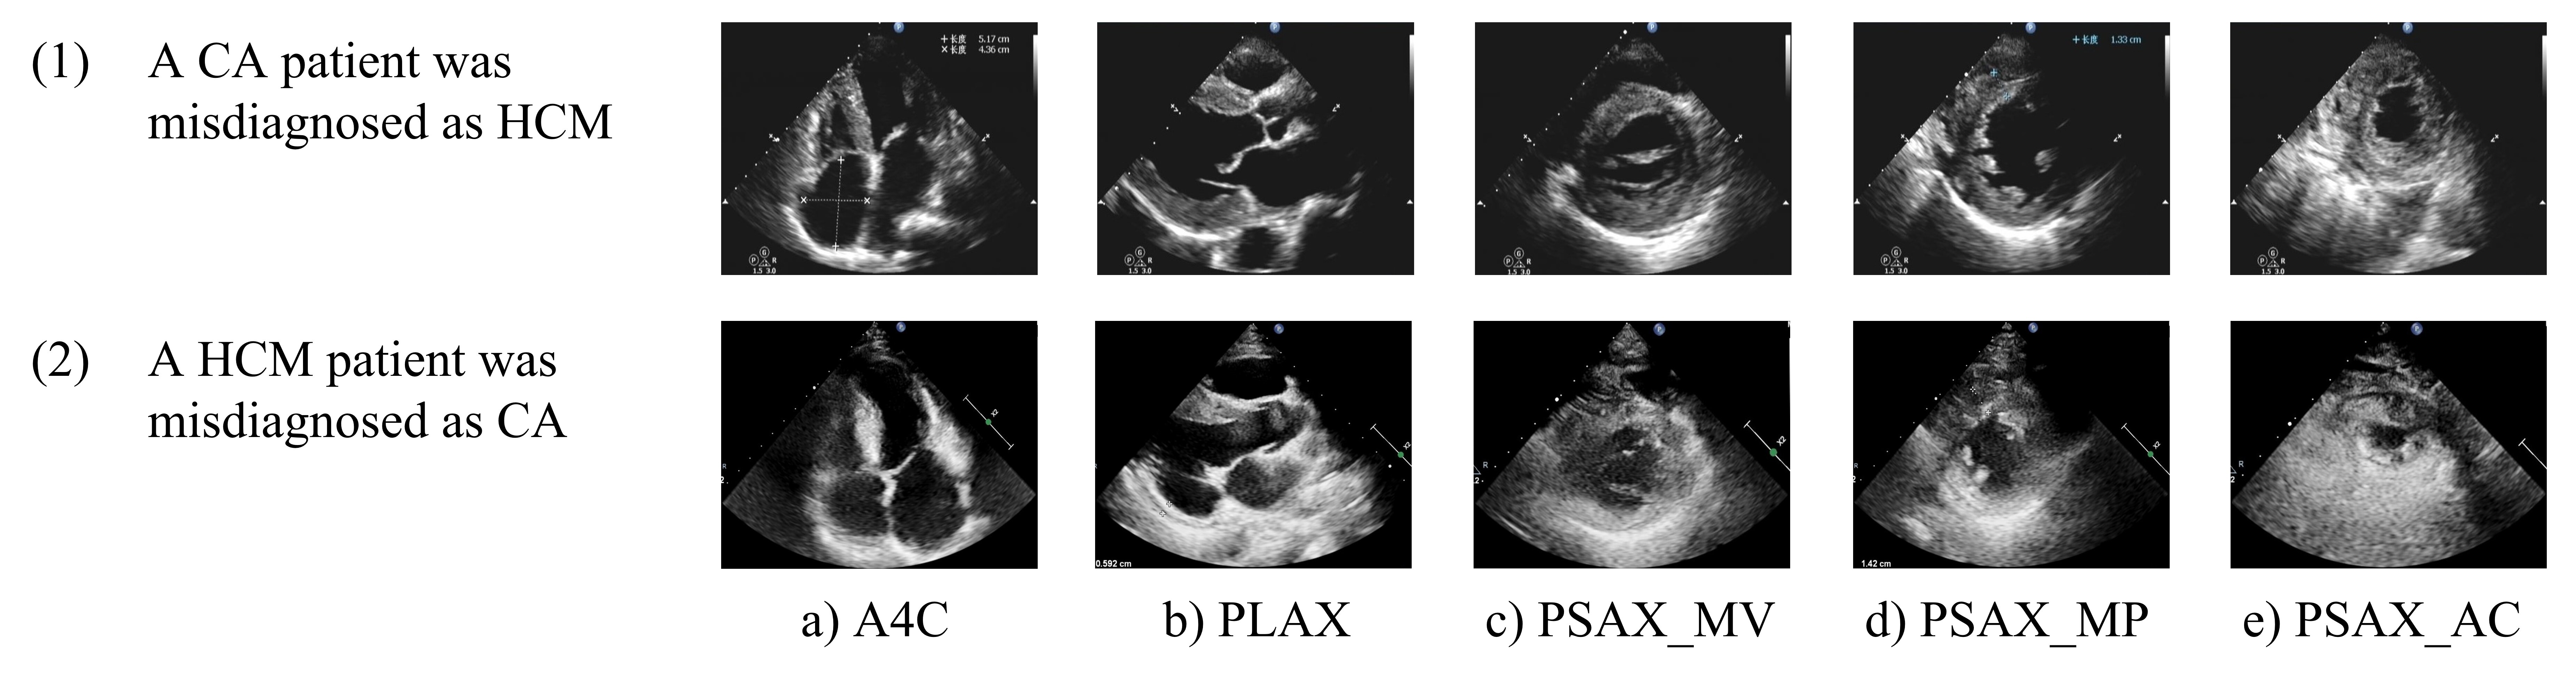

In our experimental results, we also identified three cases of CA patients misdiagnosed as having HCM based on echocardiography images. Examination of these images revealed distinct characteristics contributing to these misdiagnoses. For instance, as observed in Fig. 9, misdiagnosed CA patients exhibited low image gain, poor recognition of myocardial echo features, and thickened myocardium. Conversely, another patient with HCM was misdiagnosed as having CA due to excessively high image gain, poor image quality, and significant echo noise in the myocardium, resulting in an unclear display of the myocardial boundary. Our study yielded an accuracy rate of 0.905 in identifying HCM and CA based on static 5-view echocardiography images, which is competitive compared to diagnoses made by senior sonographers. Referring to the work of Yu et al. [bib0], our study further selected specific views, including PSAX_MV and PSAX_MP and PSAX_AC, to better reflect the differences between HCM and CA in terms of myocardial echo, thickness, distribution, and pericardial condition. However, as demonstrated by the misdiagnosed cases, slight differences in echocardiography may affect the differentiation between the two conditions.